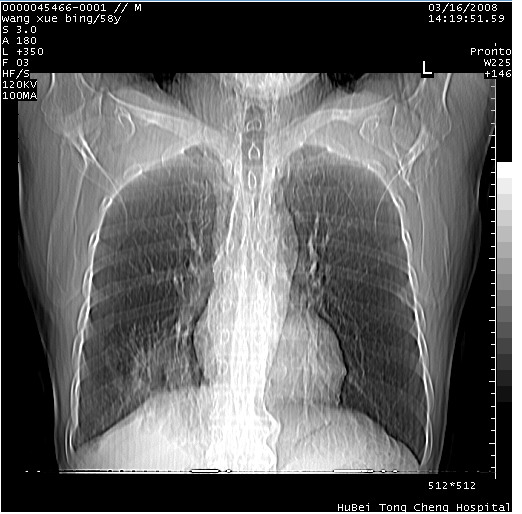

患者 男,58岁。咳嗽、咯血3月余。

胸部cr x线片提示:1)右下肺脓肿。2)右下肺周围型肺癌不排除。建议:行ct扫描检查。